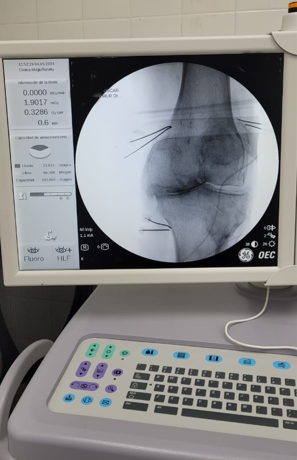

Paciente con dolor intenso por artrosis severa de rodilla

Por la morbimortalidad de la cirugía, se procede a realizar en Tidol un tratamiento con radiofrecuencia, debido al dolor intenso que le impedía la marcha.

Luego del procedimiento, el paciente deja de tomar los calmantes que se encontraba tomando para el dolor intenso y mejora su patología dolorosa.